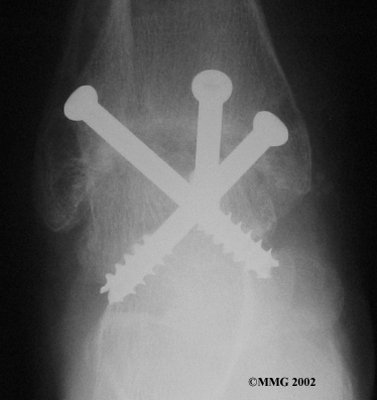

It is important when the surfaces are removed that the angles of the cut surfaces are correct. When the tibia is brought against the talus, the foot should be at a right angle to the lower leg. Once the cuts are made the bones must be held in place while they fuse. This can be done using large metal screws and metal plates if necessary. The screws are usually under the skin and are not removed unless they begin to rub and cause pain.

Inserting the screws

After ankle fusion, the physical therapists at FYZICAL-Galleria Therapy & Balance Centers can help you learn to walk smoothly and without a limp. Although time needed for recovery varies among patients, an ankle brace will typically replace your cast after eight to 12 weeks. Your surgeon will take X-rays frequently to see if the bones are fusing together. You will probably need to use  crutches during the time you wear the cast. As the fusion grows stronger, you will begin to put more weight on your foot when walking.